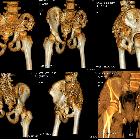

- pelvis

Plain radiograph and CT

- intramedullary or subcortical lucent foci may be the earliest manifestation

- this progresses to profound osteolysis with resorption of affected bone and lack of compensatory osteoblastic activity or periosteal reaction